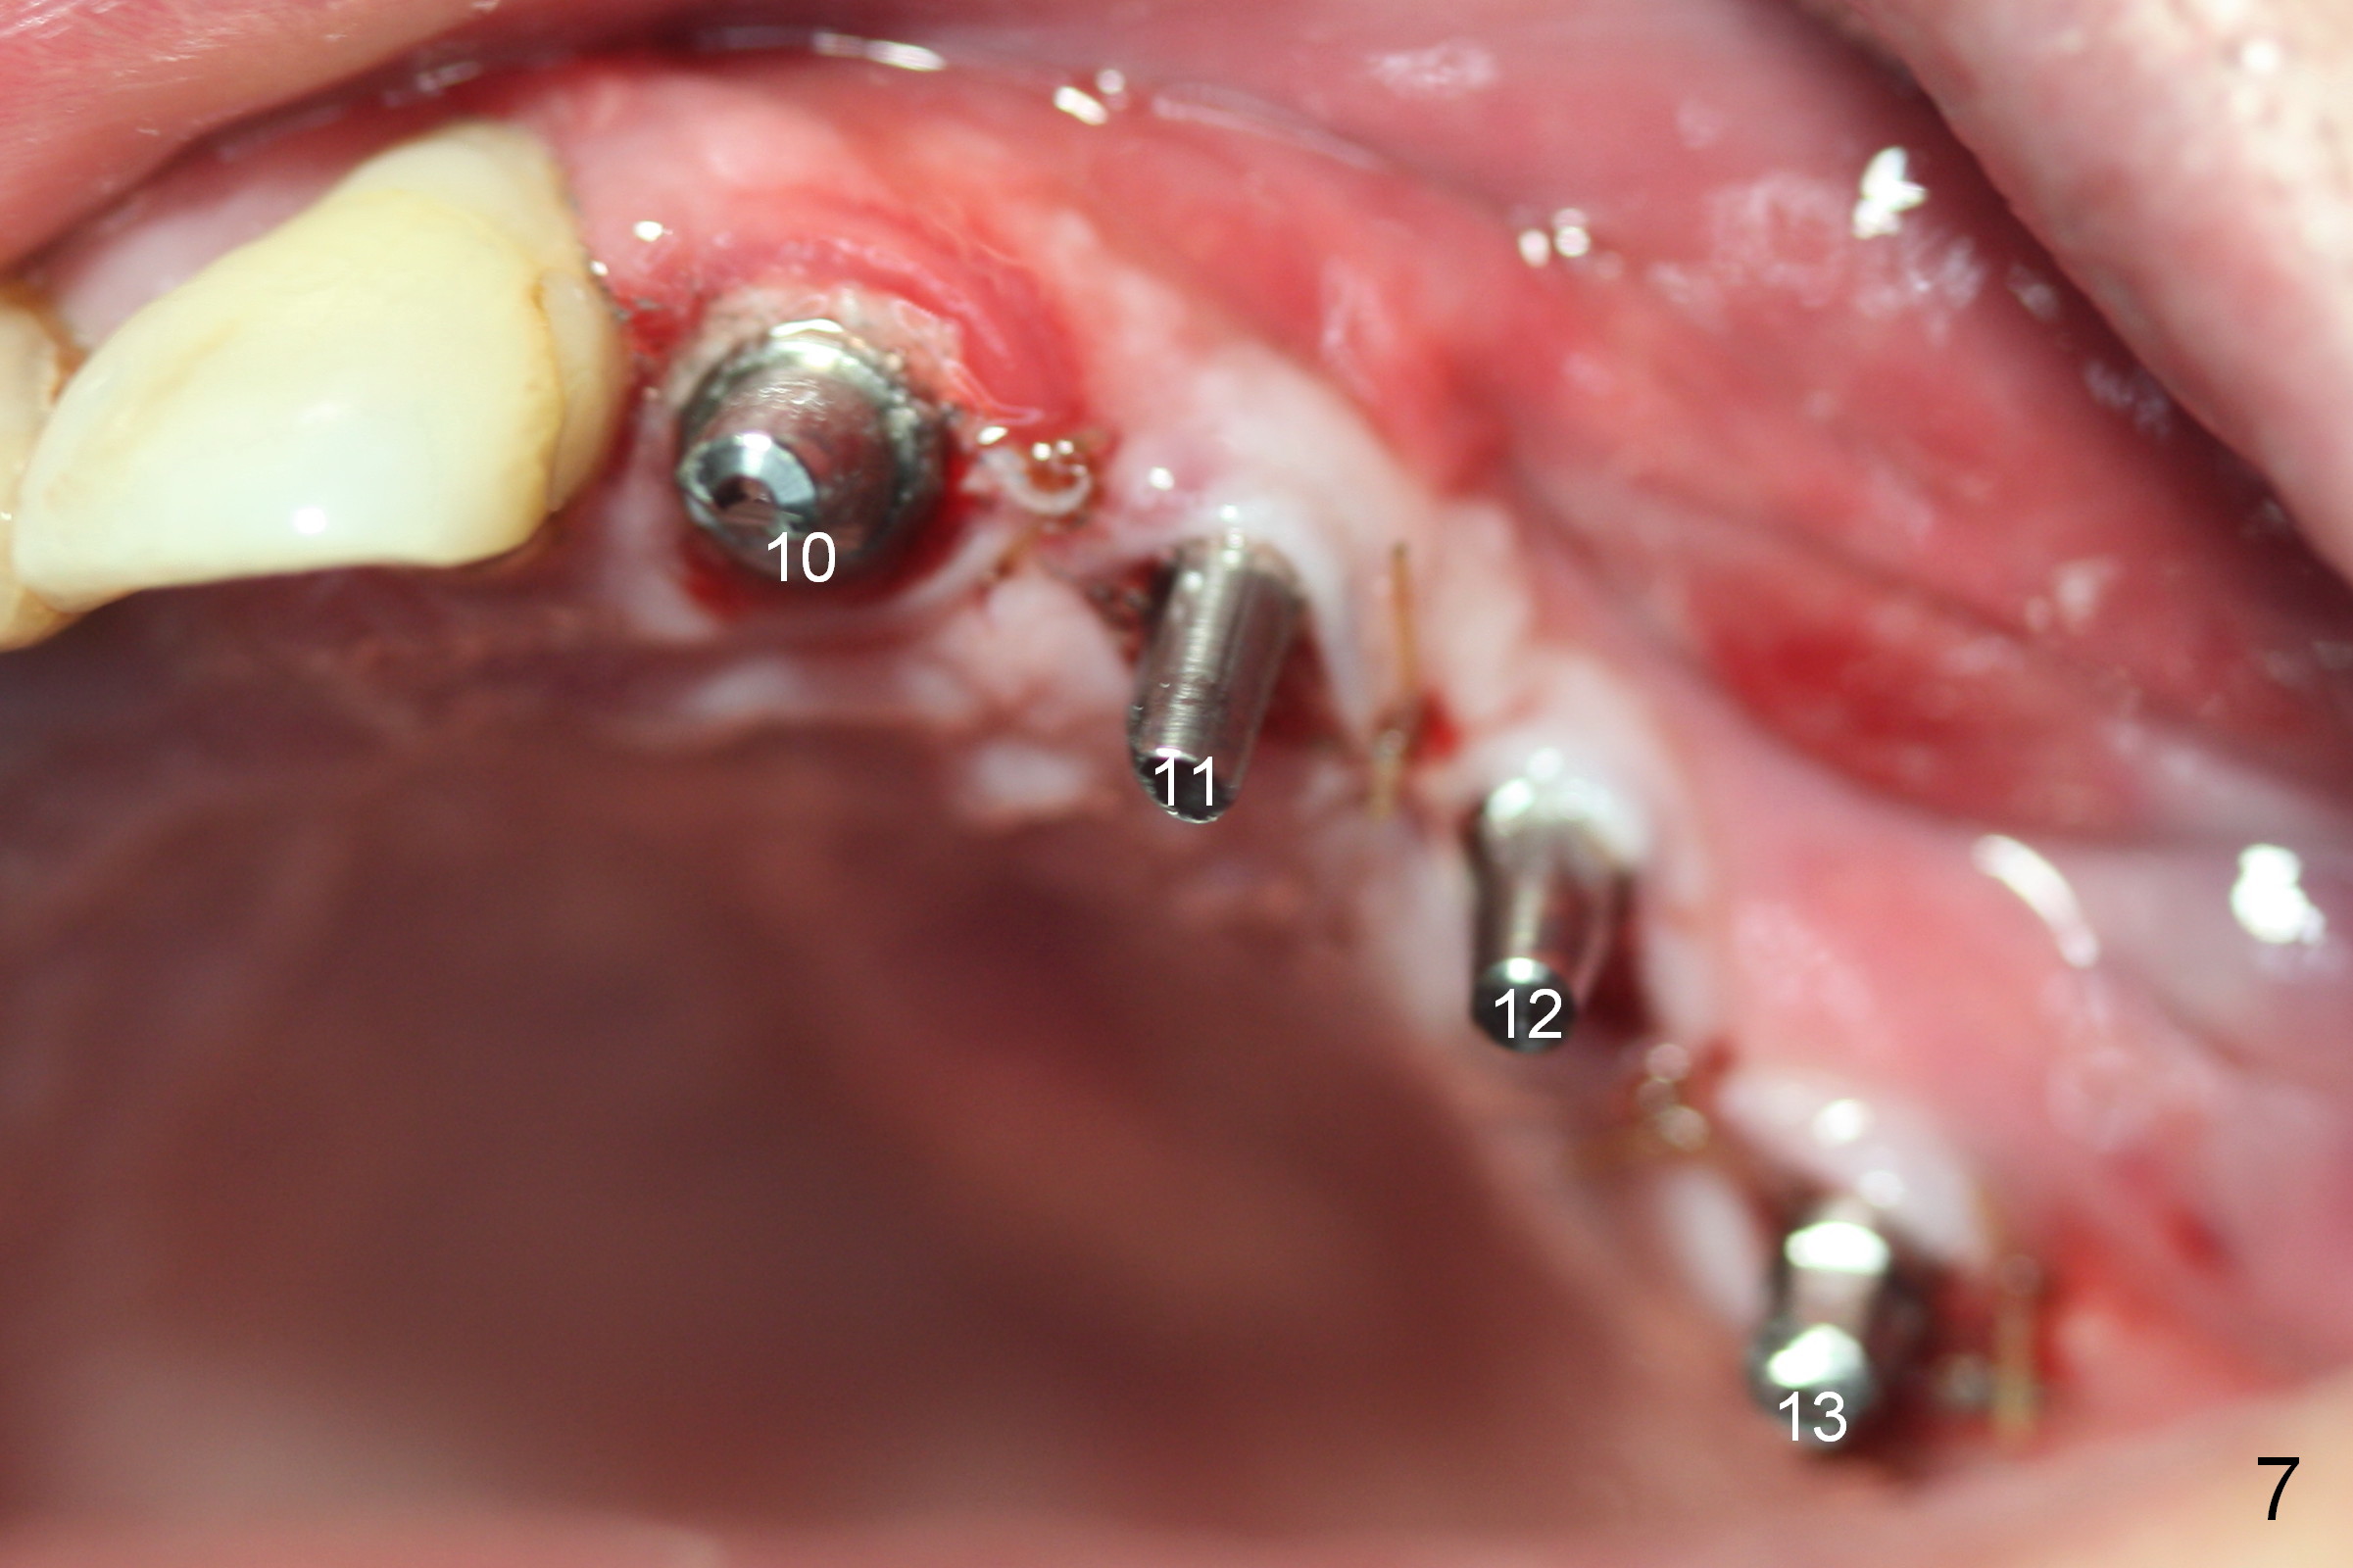

When the patient returns for implant placement (2nd visit after initial exam), he reveals that he is a dental phobic. He requests placement of 4 implants in the upper left quadrant, instead of 2. Narrow ridge is unexpected in the canine and premolar area (Fig.1). Limited bone height at #13 (Fig.3 arrowheads: sinus floor) is found when initial drills are in place (Fig.2,3). A 2-piece implant (4.5x17 mm tissue-level) is placed at #10 after extraction, while 1-piece implants are placed at 11 (3x17 mm (tissue-level, 15 °) and 12 and 13 (bone-level, 2.5x14, 12 mm, respectively; Fig.4,5). In fact the 1 piece implant at #13 is not completely placed (Fig.5). It is removed, the apical 3 threads are cut off (Fig.6 <, since a shorter implant was unavailable in the office) and the remaining implant is re-inserted. The insertion torques of the 4 implants are ~ 60, ~ 35, < 35 and 15 Ncm, respectively. After adjustment (Fig.7), immediate provisionals are fabricated at #10 and 11 (Fig.8, later splinted with composite), while perio dressing is applied around the implants at #12 and 13 and the provisionals at #10 and 11. There is no nasal hemorrhage postop. Although the perio dressing is loose 1 week postop (Fig.9), it is not removed. When the upper lip fissure (Fig.9 <) heals, provisionals at #12 and 13 are planned to be splinted to the other two ones. Two weeks postop, the upper lip fissure heals, the perio dressing dislodges and the implants at #12 and 13 are stable (Fig.10). After abutment height adjustment, a splinted provisional is fabricated over these 2.5 mm 1-piece implants (Fig.11).